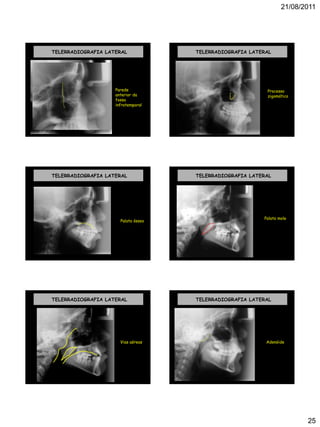

TELERRADIOGRAFIA LATERAL

Parede

anterior da

fossa

infratemporal

Processo

zigomático

Palato ósseo

Palato mole

Vias aéreas

Adenóide